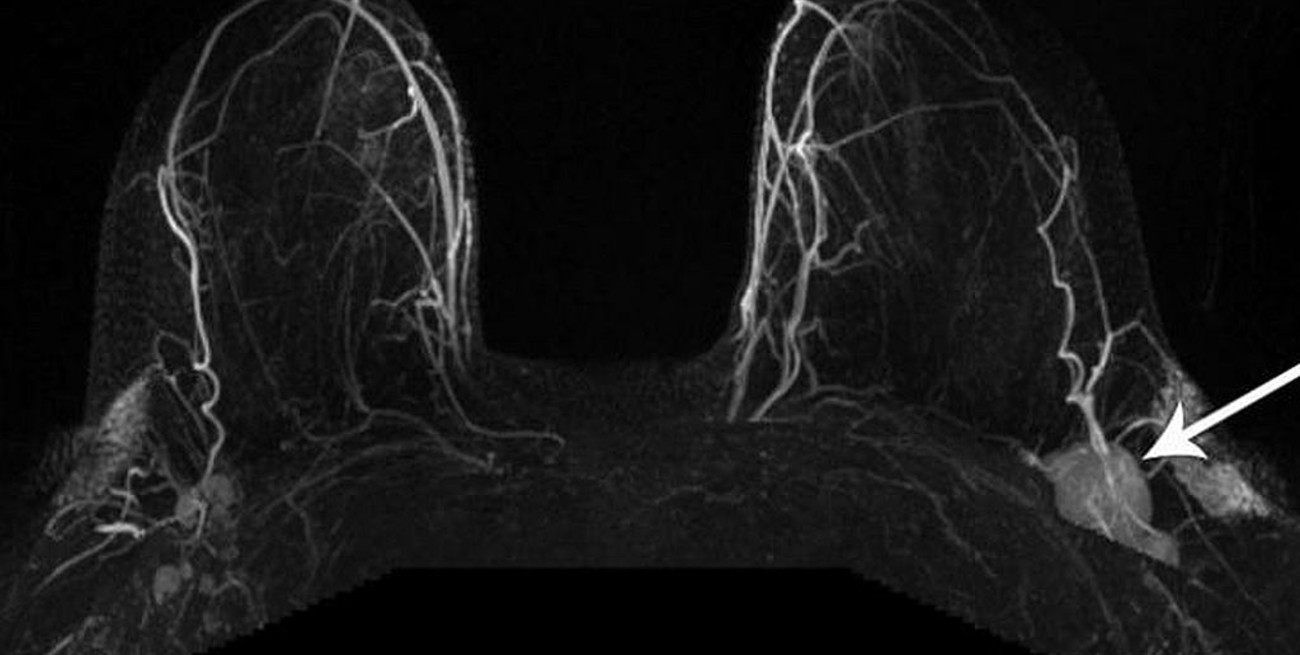

Esta mamografía, tomada después de que una paciente recibió la vacuna contra el covid-19, muestra un ganglio linfático inflamado. Situaciones similares habían estado sucediendo en los centros de mamografías de todo el país. A medida que los radiólogos compararon notas con sus colegas, se empezó a correr la voz. «Todos empezamos a hablar de ello, y fue como un incendio forestal», dijo la Dra. Connie Lehman, jefa de Imágenes Mamarias en el Departamento de Radiología del Massachusetts General Hospital. «No puedo decirte cuántas mujeres muestran nódulos en las mamografías y muchos pensaron que no sería tan común», dijo Lehman, quien también es profesora de Radiología en la Escuela de Medicina de Harvard.